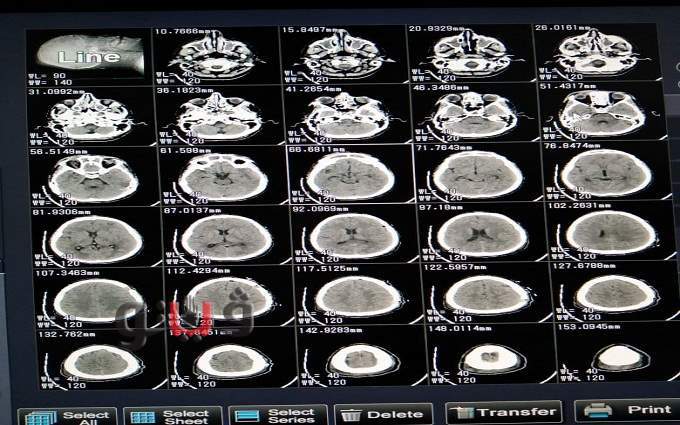

وكان الشاب يعاني من تشنجات مستمرة مع اضطراب شديد في درجة الوعي علي نظام جلاكسو للغيبوبة (GCS8/15)، مع شلل تام بالناحية اليمني من الجسم، وفقد للكلام (Aphasia)، منذ ١٠ أيام وذلك نتيجة وجود تجمع صديدي تحت الأم الجافية، الناتج عن إلتهابات مزمنة بالجيوب الأنفية، وذلك بعد إجراء الفحوصات والأشعة اللازمة.

وقام الفريق الطبي بإجراء تفريغ للصديد، وتم أخذ عينة لعمل مزرعة، والحالة الآن مستقرة وتحت الملاحظة الطبية، بإشراف مدير المستشفي.